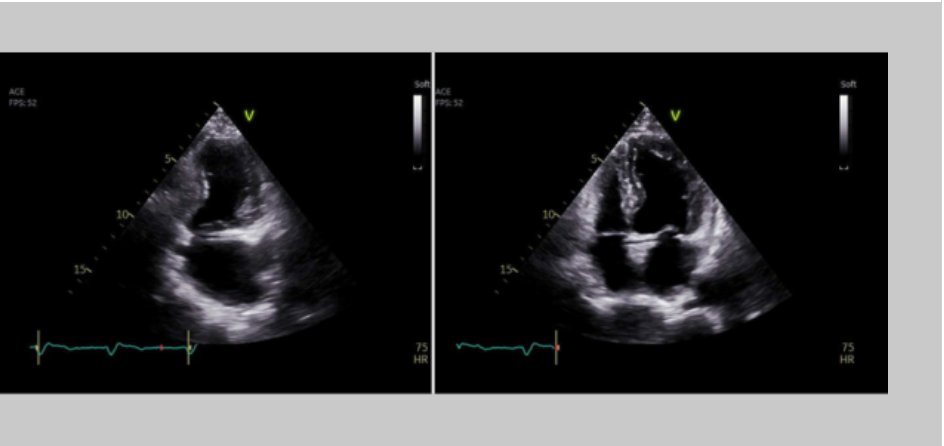

#ImageoftheWeek This week's quiz was submitted by André Lobo at al. from the Cardiology Department, Unidade Local de Saúde Gaia e Espinho, Vila Nova de Gaia, 🇵🇹 In the presented #echofirst images, which finding is identifiable? ☑️shorturl.at/QkRbt @EACVIPresident

echo_stepbystep's tweet image. #ImageoftheWeek This week's quiz was submitted by André Lobo at al. from the Cardiology Department, Unidade Local de Saúde Gaia e Espinho, Vila Nova de Gaia, 🇵🇹

In the presented #echofirst images, which finding is identifiable? ☑️shorturl.at/QkRbt